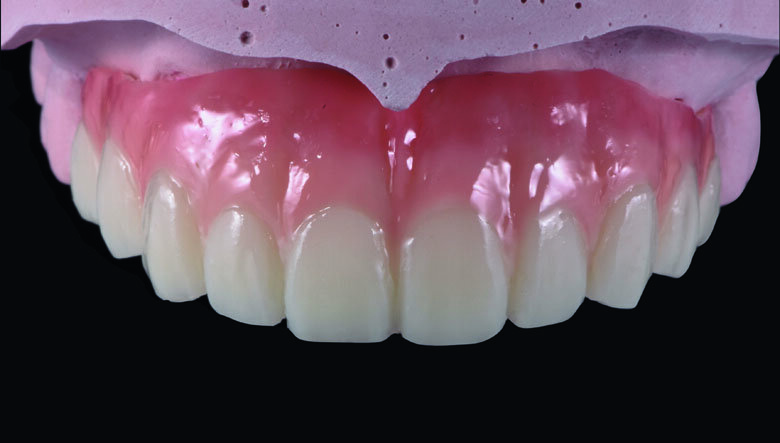

Fig 19. Completed Provisional Profile Prosthesis with gingival aesthetics that mimic nature

Preparation cast with a diagnostic wax-up ca st was sent to a local laboratory for scanning and transforming into STL (Stereolithography) digital impression file. (Fig 8,9.) Two sets of STL impressions were super-imposed in the software in order to subtract the overlapping data. This process was done in order to transform the diagnostic wax-up into the STL digital impression. Consequently, the STL data was sent to the laboratory for milling. (Fig10.) A monochromatic milled-PMMA temporary bridge was fabricated in a local laboratory and returned to the dentist for composite layering. (Fig 11.) Gingival cutback was made to create sufficient gingival space for pink composite layering (Fig 12). Prior to composite layering CeraResin Bond 1 was applied and left for 10 seconds to prime the surface, followed by application of CeraResin Bond 2 for 10 seconds and light cured for 20 seconds (Fig 13.). Ceramage Indirect Composite gingival shade GUM-O (GUM Opaque) was applied to mask the color of PMMA (Fig 14.). GUM-D (GUM Dark) was applied on the attached gingiva area to the buccal flange (Fig 15.). GUM-L (GUM Light) was applied in the region of free gingiva (Fig 16.). F-GUM-R (Flowable GUM Red) and F-W (Flowable GUM White) were painted to mimic the mucogingival junction and vascular alveolar mucosa (Fig 17.) GUM-T (GUM Translucent) was applied to reproduce of reddish translucent gingiva areas (Fig 18) to achieve natural gingival aesthetics.

Contouring, Finishing and Polishing of temporary restoration

Meticulous finishing and polishing of the restoration is a crucial step to achieving the desired aesthetics. Dura-Green stone was used to contour the macro anatomical details while the Robot Carbide Fissure Bur was used to shape the interproximal and papilla areas. The course silicone points followed by Dura-Polishing paste Al2O3 with a medium strong brush was used to finish and pre-polish the restoration. Dura-Polish DIA, diamond polishing paste was applied with a fine brush followed by the cotton buff to achieve the final high-luster polishing (Fig 19.)1.